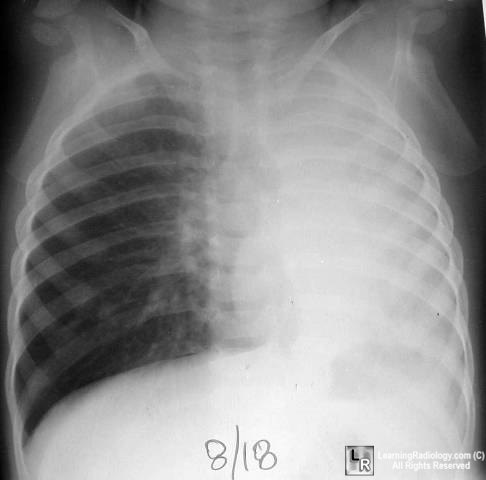

Pictorial Differential Diagnoses

Click on the tabs to see the differential; click on the photo to enlarge;

click on the text beneath the photo for more information

Pulmonary Differentials